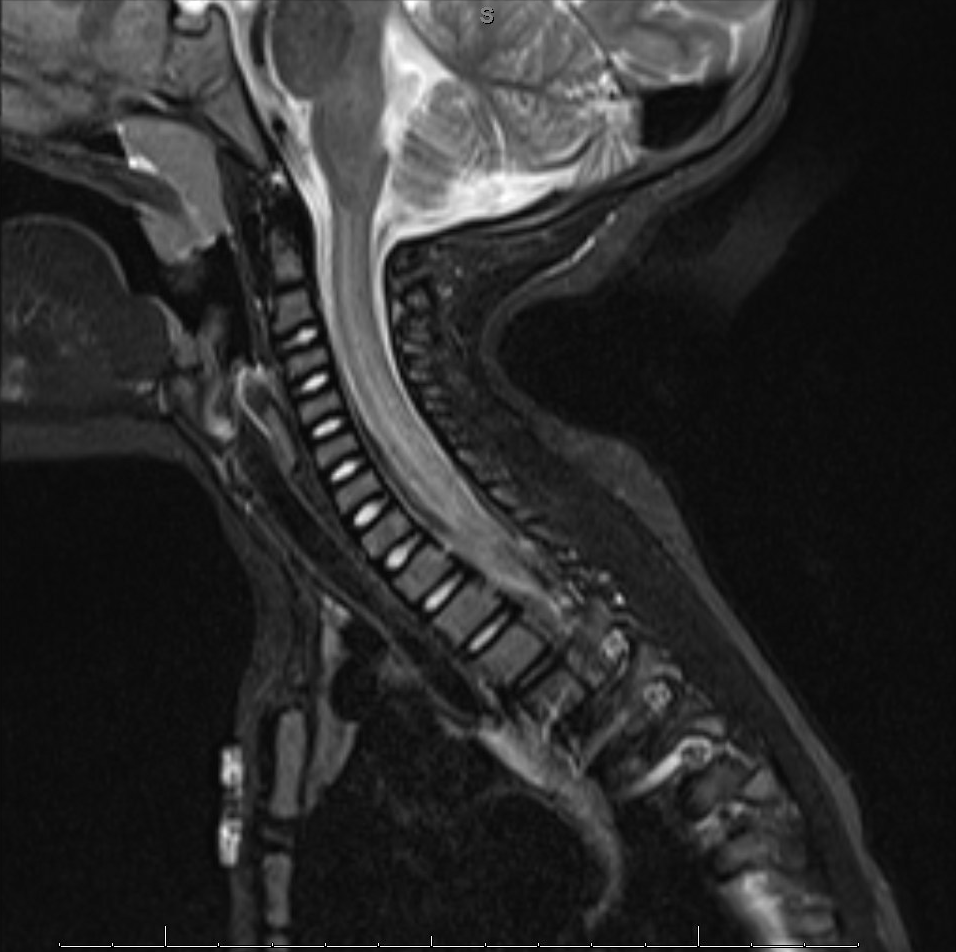

Magnetic resonance imaging (MRI) of the cervical spine and right brachial plexus showed abnormal T2-weighted hyperintensity, most prominent at the craniocervical junction (Figure 1). MRI of the thoracic and lumbar spine showed abnormalities of the cauda equina similar to the cervical spine findings (Figure 2). Brachial plexus MRI findings were normal.

Figure 1. Sagittal MRI at C5-6 showing an abnormal heterogeneous speckled appearance.